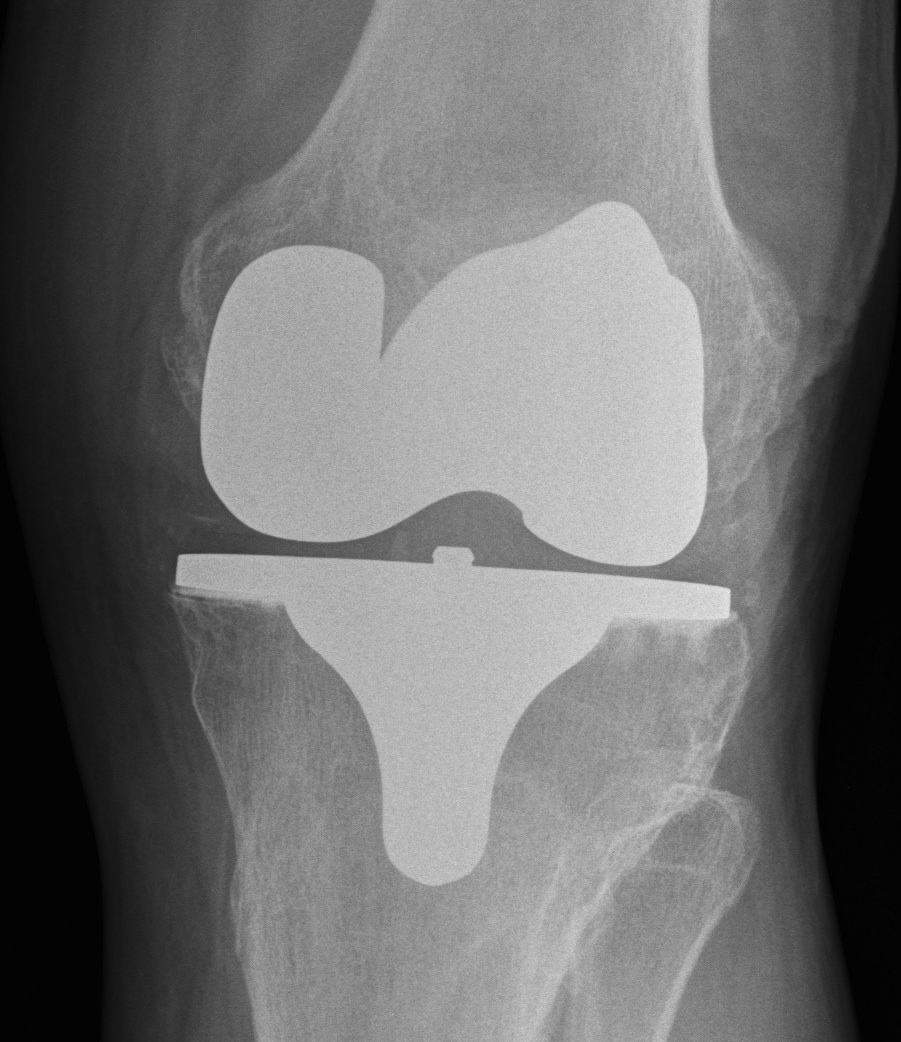

Varus-Valgus instability

Causes

A. Iatrogenic collateral ligament injury

Options

- advance / imbricate / augment / reconstruct collateral

- full revision to VVC / CCK constrained implant

B. Failure to balance knee

Cause

- under release deformity in the concavity

Management

- increase poly thickness, further releases in concavity

C. Insufficient poly / loosening over time

Diagnose

- equal varus and valgus instability

- increase poly thickness